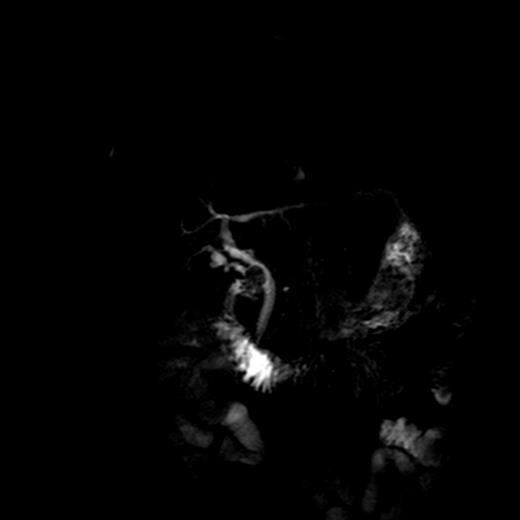

An ultrasound-guided core biopsy was attempted, but failed due to technical reasons. A CT-guided core biopsy of Segment 6 lesion was successful, but an interval reduction in the size of the liver lesions was noted. A magnetic resonance cholangiopancreatography (MRCP) to reassess the liver and biliary tree was therefore planned. MRCP revealed a persistent stricture at the cystic duct CBD junction (Fig. 3). The histology from the core biopsies of the liver revealed a granulomatous process with Langhans giant cells (Fig. 4). The pathologists opined that although rare, mycobacterial involvement should be considered as a differential diagnosis. This coupled with the spontaneous reduction in the size of the liver lesions led to a consensus opinion for a surgical exploration to resect the biliary stricture and re-biopsy the liver lesions.